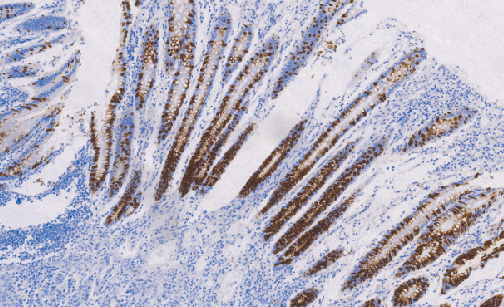

Muc-2 Glycoprotein鼠抗人粘液素糖蛋白2单克隆抗体

粘糖蛋白2是一种高分子量的糖蛋白,其合成和分泌是腺上皮组织的特征之一,与消化道肿瘤的发生相关。在正常组织中,粘糖蛋白2主要表达于小肠腺上皮、涎腺上皮和乳腺上皮。同时,在结肠癌和胃癌等肿瘤中也呈现阳性表达。

- 阳性部位:胞质

- 适用组织:石蜡组织

- 预处理:热修复